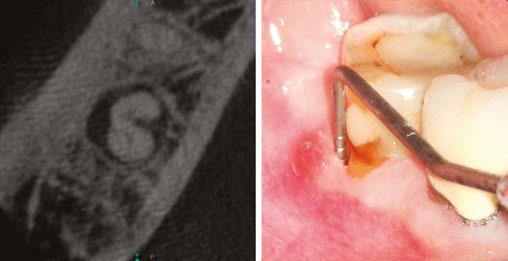

Figures 1A-1C: 1A. Preoperative X-ray. 1B. Immediate postoperative X-ray. 1C. Follow-up after 9 years and 10 months

Periapical radiographs and medical records corresponding to 48 teeth with IRR were collected from five different dental offices. The following aspects of the IRR were then analyzed: number of tooth in which it was found, location, presence or absence of periapical radiolucency, shape of the affected dentin walls, type of treatment performed, filling technique used, degree of adaptation of the filling to the resorption, presence of perforation communicating with the periodontium. Of the 48 cases diagnosed with IRR, all have been endodontically treated, and 29 of them have received initial treatments and 19 retreatments. Of the total number of cases, 29 had long-term follow-ups, while 19 do not have them.

Of the total, 29 had long-term radiographic follow-ups that ranged from a minimum of 6 months to a maximum of 25 years, with an average of 5 years, 4 months. Of the cases with radiographic follow-ups, 28 were considered successful and one failure (Table 2). Of the successful cases, 17 corresponded to treatments and 11 to retreatments (Figures 1A, 1B, 1C, and 2A, 2B, 2C). The tooth considered failed was a retreatment.

IRR is a disease of the dental pulp that affects the dentin wall, which is reabsorbed by clastic action. It can occur in any tooth, although its presence is more frequent in those more susceptible to different kind of trauma. According to what was observed in this study, the upper incisors and the lower first molars are the most likely to present IRR, and this could be since the former are the ones that often suffer traumatic injuries, while the lower molars suffer more the action of orthodontic forces (Figures 3A, 3B, 3C).

The radiographic appearances that generates the IRR are varied. The most common one observed in the present study was a circular shape with regular and symmetrical walls specially in single-rooted teeth (Figure 4A), although there were also some

Figures 2A-2C: 2A. Preoperative X-ray. 2B. Immediate postoperative X-ray. 2C. Follow-up after 18 years and 6 months

Figures 3A-3C: 3A. Preoperative X-ray. 3B. Immediate postoperative X-ray. 3C. Follow-up after 4 years

irregular ones with asymmetrical walls (Figure 4B). In molars, when resorption affects the pulp chamber, it was commonly seen as an irregularly shaped radiolucent cavity2 (Figure 4C).

Figure 4A-4C: 4A. Maxillary lateral incisor with an internal resorption at the coronal third. 4B. Mandibular canine with an internal resorption in the middle-apical area. 4C. Mandibular molar with an irregular internal resorption in the coronal portion Figures 5A-5C:

5A. Preoperative X-ray. 5B. Immediate postoperative X-ray. 5C. Follow-up after 1 year and 9 months EP